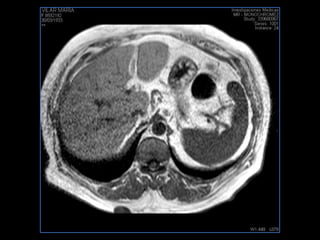

PROTOCOLO abdomen COR T2, AXIAL supresion grasa AX T1 +SAG T2  CON   GADOLINIO :  COR T1+AX T1(DIN) SAT: NO  FASE: RL THK: 6MM  COIL:  GAP: (FACTOR 1.4) 2MM FOV: 40 CM NEX:2 SINCRONIZACION RESPIRATORIA EN 3 O 4 CICLOS ALE

PROTOCOLO hígado graso AXIAL in phase y out phase AX T1 y AX fat sat +SAG T2  CON   GADOLINIO :  COR T1+AX T1(DIN) SAT: NO  FASE: RL THK: 4MM  COIL:  GAP: (FACTOR 1.4)  FOV: 40 CM NEX:2 SINCRONIZACION RESPIRATORIA EN 3 O 4 CICLOS ALE

PROTOCOLO hemocromatosis AXIAL supresión grasa /AX multieco en higado COR T2 AX T1 +SAG T2  CON   GADOLINIO :  COR T1+AX T1 SAT: NO  FASE: RL THK: 4MM  COIL:  GAP: (FACTOR 1.4) 1MM FOV: 40 CM NEX:2 SINCRONIZACION RESPIRATORIA EN 3 O 4 CICLOS ALE

PROTOCOLO pancreas/ riñon AXIAL fat sat /AX in phase out phase AX T1 +SAG T2  COR T2, CON   GADOLINIO :  COR T1+AX T1(DIN) SAT: NO  FASE: RL THK: 4MM  COIL:  GAP: (FACTOR 1.4) 1MM FOV: 40 CM NEX:2 SINCRONIZACION RESPIRATORIA EN 3 O 4 CICLOS ALE

resonancia de abdomen